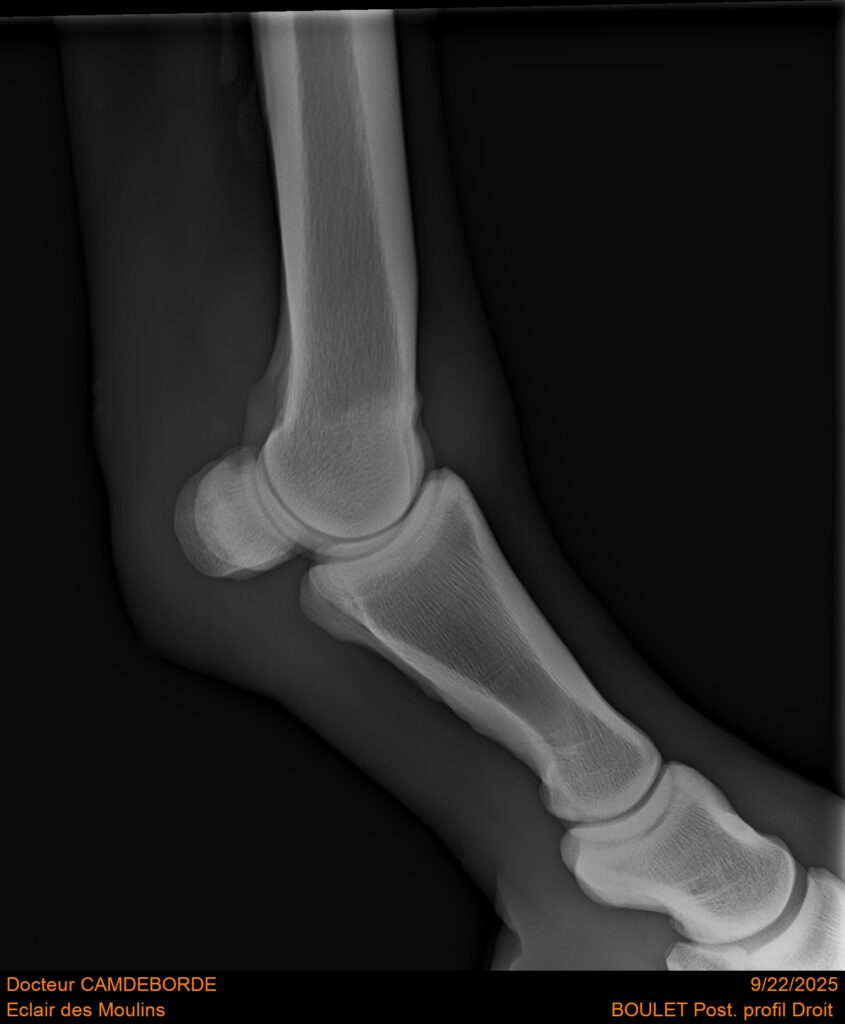

10 K ✨ TOP cheval pour épreuve Amateur ! ECLAIR DES MOULINS, selle Français de 11 ans. Classé sur 1m05. Idéal pour aller faire jusqu’à 110 voir 115, cheval pas usé (une vingtaines de parcours). Très gentil au quotidien, cheval de famille. Courageux et respectueux à l’obstacle. Bien dressé, change de pieds. Bilan pieds, boulets, jarrets, grassets et visite clinique effectuée cette semaine. il peut vivre au box comme au champs, cheval rustique. toise environ 1m60 porteur. Pour le compte de son propriétaire car manque de temps.

RADIOS ET CLINIQUE